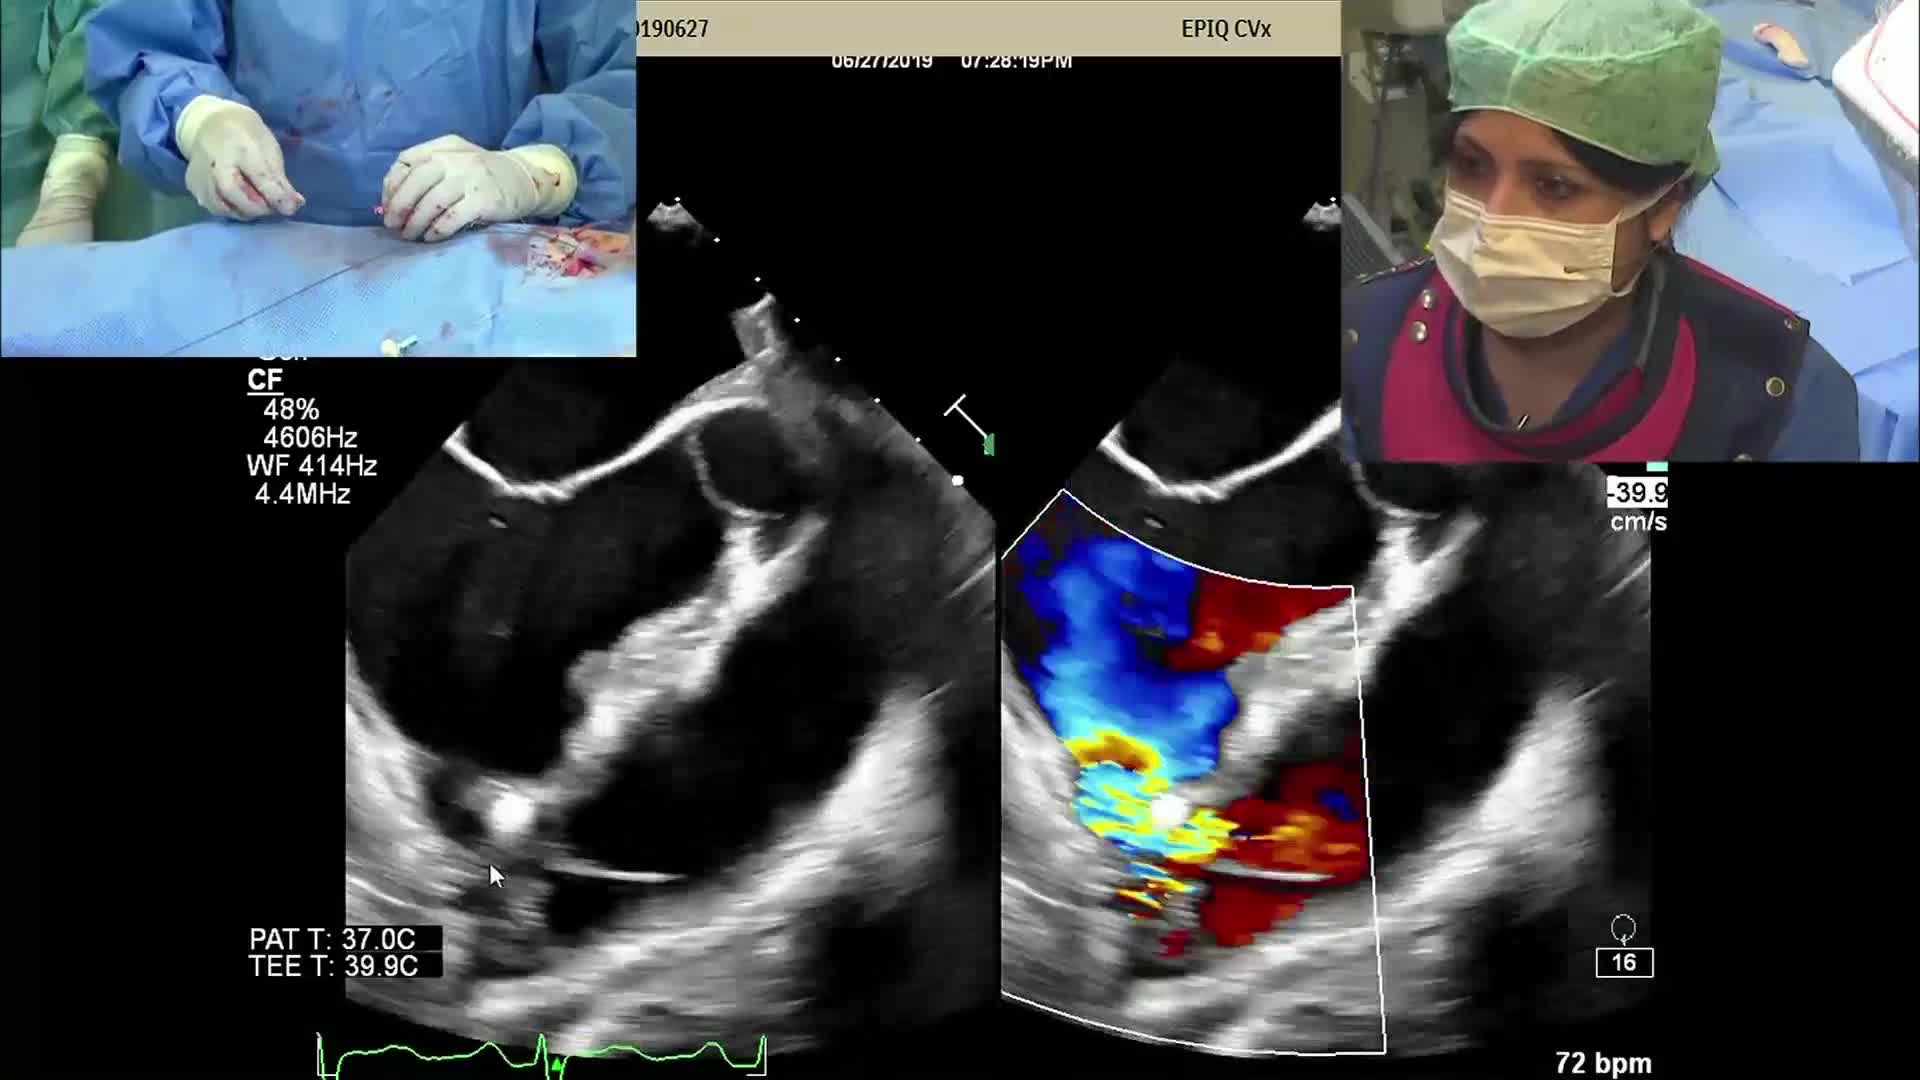

CSI CATHLAB LIVE - VSD CLOSURE WITH THE NEW OCCLUTECH PMVSD OCCLUDER (ANTEGRADE APPROACH)